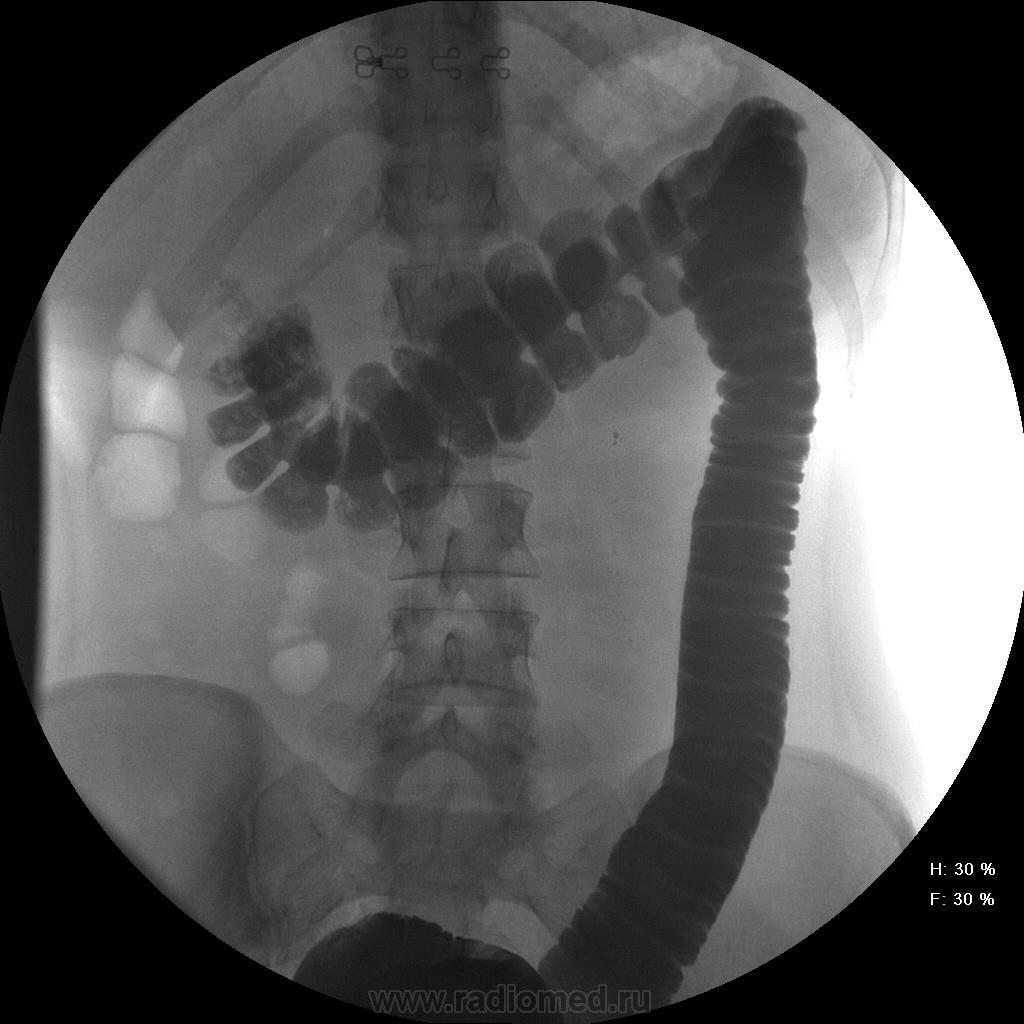

Девушка, 27 лет, жалуется на периодические боли в правой подвздошной области, области паха справа. Во время этого идет нарушение стула - то слабит, то несколько дней не может ходить в туалет, вздутие кишечника. Жалобы несколько лет . Обследованна кем только можно. Хирург посоветовал ирригоскопию. Работа достаточно нервная. До первого случая данных проблем , за неделю, проходила сан лечение в пансионате ( для поднятия общего иммунитета - так говорит), был курс клизм с травами - сама думает, что это не связанно.

Цепочка тенюшек - это наша "гордость)" следы от контраста после гистеросальпингоскопии. чтоб вымыть ,надо разбирать стол , а это только с представителем сименса. вот так.) а правые отделы толстой кишки на расширены? я кроме лополнительной петли сигмы сам ничего не вижу. несколько настораживает некоторое расширение правых отделов кишки- может за счет запоров, которые случаются у девушки? не хочется что то пропустить.

При таких симптомах ищи "бабьи дела", может быть хр. аппедицит. Необходимо определиться с характером и продолжительностью болей. Наиболее вероятнно - недостаточность функции Баугиневой заслонки. При указании или подозрении на эту патологию меняется методика обследования. Ваши снимки расположены хаотично, а не по мере заполнения кишечника. При подзрении на недостаточность функции Баугиневой заслонки, по рекомедации Шнигера, заполняется толстая кишка до печёночного угла, а далше только с помощью глубокой пальпации. Если в этом случае удаётся провести контраст в тонкую кишку или при опорожнеии кишечника контраст попадает в тонкую - пиши недостаточность Баугиневой заслонки.

1.Даже сам Витебский признавал оносительность как клапана Баугиньевой заслонки...

2. У Вашей больной типичный дисбактериоз.....эту проблему Вы не исключали? еще не известно...что это были за клизмы...и какую флору она с ними получила...или какой избавилась...

Признак долихосигмы - это наличие т.н. симптома "трехстволки", есть это - есть и долихосигма. В данном случае такой вариант имеет место быть.

Не буду уточнять конкретно, ну уж очень близкий человек на курорте попался на такую же удочку (повышение иммунитета), и после этого такие же жалобы, боли...На ирригуше написал норму, хотя проктолог на ней увидел колит. На колоноскопии - тоже колит, что-то назначали. но прошло само собой. И первопричина, я думаю, эти орошения. Попытаюсь сейчас найти снимки, сфоткать (как получится). Короче на фоне окна тюли и улицы...Да, это было в 2001 году. До сегодняшнего дня - жалоб нет. А на представленных снимках я бы никчему бы не придрался.